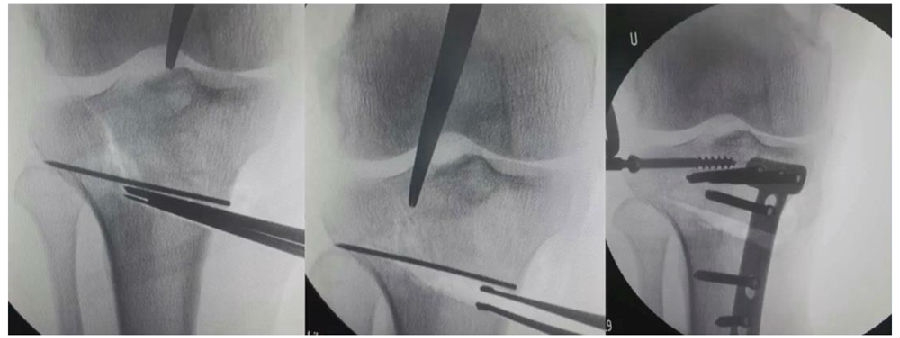

(3)Ⅲ型骨折

首先要把截骨撑开钳拿下来,此时骨折端会自动复位,然后再由外向内侧打入一颗拉力螺钉,将胫骨平台做临时固定,然后再进一步的用摆锯锯或是用骨刀打,保留1cm的合页,最后再进行撑开,做内固定。同样要求患者做结构植骨加延迟负重。

截骨偏前,截骨线过短;Ⅲ型骨折;保留1cm合页

结构植骨,外侧拉力钉固定